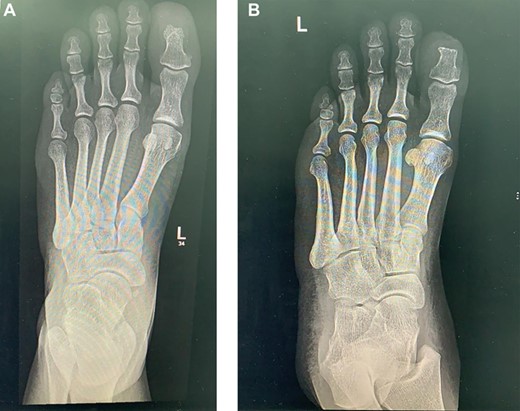

The laboratory data included a white blood cell count of 6000/μl, hemoglobin of 10.5 g/dl, platelet count of 233 × 10/μl, blood glucose 121 mg/dl, blood urine nitrogen 46 mg/dl, serum creatinine 69 mg/dl, sodium 138 mmol/L, potassium 3.8 mmol/L, serum albumin 3.4 g/dl, erythrocyte sedimentation rate 73 mm/h, and C-reactive protein 15.6 mg/dl. The X-ray of lower extremity revealed no significant abnormality (Fig. 1).